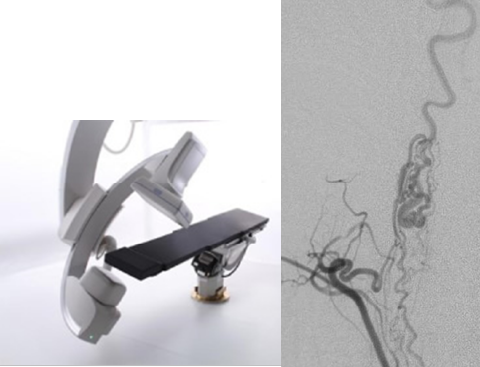

脊髄血管奇形は非常に稀な疾患ですが、北大脳神経外科は歴史的に多くの診療実績を有しております。脊髄動静脈奇形、傍髄動静脈瘻、硬膜動静脈瘻、硬膜外動静脈瘻と、大きく4つに分類される本疾患群は、病変の複雑さも様々でありそれに応じた適切な治療選択が不可欠です。当院では脊髄外科グループ、血管内(カテーテル)グループ、放射線治療科が連携し、最適な治療法をご提案します。また、必要に応じてハイブリッド手術室(血管造影装置を備えた手術室)で、術中血管造影検査を行いながら外科手術を行っており、より精密な治療が可能です。